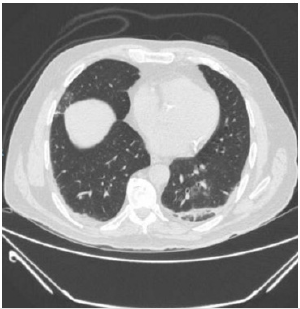

patient is identified with radiographic data from an unenhanced

chest computed tomography with multiple consolidative peripheral

opacities with ground-glass density in multiple lobes (Figures

1-6) with a peripheral distribution, which has been reported as a

common finding of SARS-CoV-2 pneumonia [6].